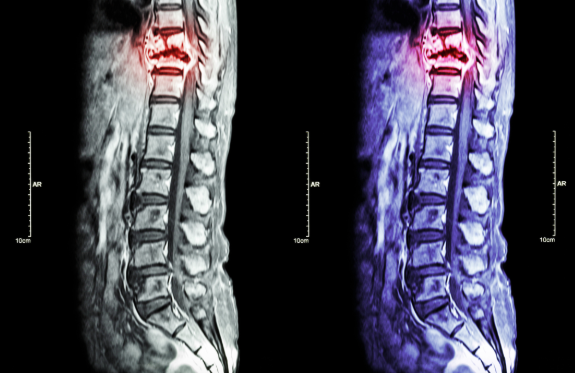

- El dolor puede ir desde el cuello hasta la parte baja de la espalda.

- La intensidad del dolor puede variar, desde una molestia leve hasta un dolor agudo e incapacitante.